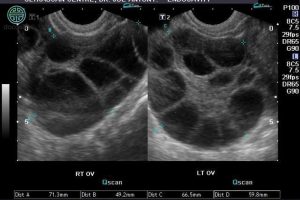

U nang buồng trứng xuất huyết là gì, có nguy hiểm không?

U nang buồng trứng xuất huyết là hiện tượng mạch máu bị vỡ ở bệnh nhân mắc u nang buồng trứng trong quá trình phóng noãn. Hãy cùng Doctor có sẵn tìm hiểu về vấn đề này trong bài viết dưới dây nhé! U nang buồng trứng xuất huyết là gì? U nang buồng trứng […]